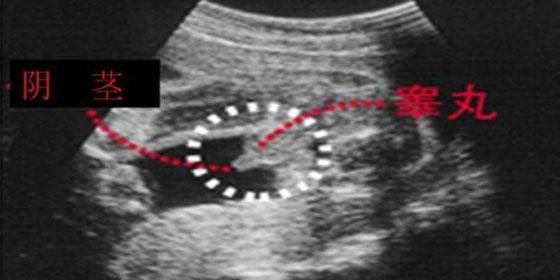

四维单子上有男女暗示 男胎儿小鸡b超显示图像

众所皆知,B超看胎儿性别是最科学,也是最准确的方法。尽管大家都知道如今国家有明文四维彩超怎么看性别?

女性妊娠24周后通过做四维彩超一般就可看出男女,看性别与胎儿的体位有关系,但如果胎儿双腿紧闭就无法判断

如何通过四维彩超单看胎儿性别 1、看四维彩超单上的字母看男女 在彩超单上,顶头最右边有两行字,是英文